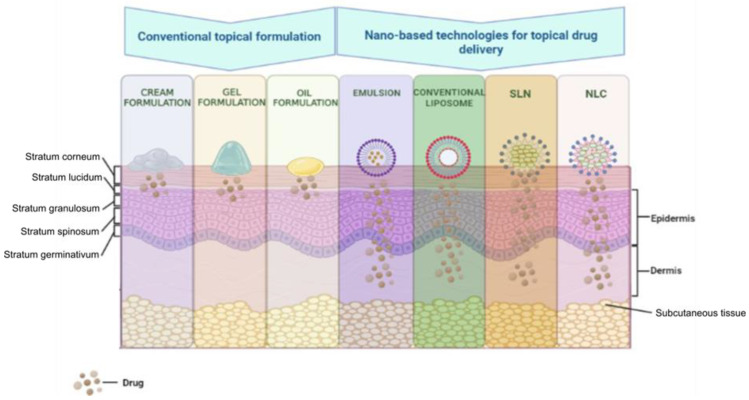

The field of cannabinoid research is expanding its boundaries more and more. The understanding of the pharmacology of these compounds and the knowledge of their beneficial effects in the treatment of pain, post-chemotherapy emesis, neuropsychiatric conditions, and dermatological conditions, in particular, stimulated researchers to address topics related to optimal formulations. Theoretically, the most promising formulations, which exceed the limitations imposed by the physico-chemical characteristics of cannabinoids, mentioned above are those that allow their administration on the skin [ref. 154]. Among these skin administration methods, we focus on those based on nanotechnology, that have, as observed in Figure 4, better penetration through skin layers than conventional formulations.

These formulations include but are not limited to lipid-based nanocarriers (liposomes, nanostructured lipid carriers, and solid lipid nanoparticles) and vesicular nanocarriers (niosomes, liposomes, transferosomes, ethosomes, and transethosomes) [ref. 210].

Due to the high lipophilic nature of cannabinoids, creams are one of their topical administration systems with multiple advantages. The topical application of cream containing CBD and CBD:THC in various proportions allowed a reduction in the symptoms of epidermolysis bullosa simplex and psoriasis [ref. 211,ref. 212].

Another delivery system for cannabinoids through the skin, with a series of improved characteristics compared to oils and creams, is to use gels. From a mechanistic point of view, gels allow the deep penetration of cannabinoids through the skin for a systemic effect. It is interesting that researchers have tried to apply different techniques to obtain constant and controllable concentrations of cannabinoids in the plasma. In this sense, in a study on a rat model of arthritis, the gel containing CBD reduced the associated inflammation, limb posture score, and thickening of the synovial membrane in a dose-dependent manner [ref. 214].

Advanced research has allowed the improvement of these forms of administration so that both gels and creams have been proposed to improve their characteristics using nanotechnology. Thus, improving the contact time with the skin, producing a uniform dispersion of the active substance, increasing the stability and bioavailability of the active substance, and high penetration through the skin are some of the qualities of the formulations improved by nanotechnology [ref. 215].

Nanoemulsion is “a system of water, oil, and amphiphile, which is a single optically isotropic and thermodynamically stable liquid solution” [ref. 216]. This type of emulsion is a formulation option that is suitable for both lipophilic and hydrophilic substances [ref. 217]. The advantages of nanoemulsions include reduced toxicity, the ability to be administered by various routes (topical, transdermal, parenteral, and others), and an increase in the stability of incorporated active substances [ref. 215,ref. 217]. Using this release system, numerous pharmaceuticals, including analgesics, anti-inflammatories, antidepressants, anti-anginal, anti-psychotics, and anti-cancer agents, have been researched and developed [ref. 217]. Recently, nanoemulsions significantly improved the skin penetration capacity of THCA and CBDA cannabinoids. This transdermal release system potentiated the stability, permeation rates, and solubility of cannabinoids. Thus, these promising results propose nanoemulsions as a strategy to improve the stability of cannabinoids in dermal formulations [ref. 189]. On the other hand, although promising, this drug delivery system also presents a series of disadvantages. The realization of nanoemulsions requires a series of special formulation techniques, which involve considerable financial efforts. In addition, there is scientific evidence that confirms a potential disruption of the integrity of the lipids of the corneous layer of the skin, a disadvantage generated by substances that further enhance the permeation of the active substance through the skin [ref. 215]. Despite these drawbacks, the research field of nanocarriers continues to develop. Thus, other nanoparticles are created, such as liposomes, to improve drug delivery skin systems.

One or more lipid layers that incorporate an aqueous phase structurally form nanoparticles called liposomes. These vesicular nanocarriers have the advantage of allowing both the topical and transdermal administration of drugs. In addition, liposomes allow the controlled release of the active substance [ref. 215]. According to some researchers, by having a higher skin deposition than other delivery systems, liposomes have superior properties relative to oil-/water-type emulsions and solutions [ref. 218].

From a mechanistic point of view, liposomes improve the topical administration of drugs by acting as a rate-limiting barrier, which prevents systemic absorption where this is not desired. Additionally, by improving the flexibility of liposomes with the help of surfactants and adding elastic lipid bilayers, these nanocarriers can serve for the transdermal administration of drugs with promising results [ref. 219]. At the same time, this delivery system allows the incorporation of highly lipophilic substances, such as cannabinoids. A recent study on an experimental canine model of chronic pain tests the subcutaneous administration of CBD in the form of liposomes. This study demonstrates that liposomal CBD produces qualifying CBD plasma concentrations that are maintained over the tested period (28 days) [ref. 220]. Accordingly, liposomes can become a successful method of administration for cannabinoids in the future due to their proven analgesic effect. However, there are also disadvantages with respect to the use of these nanocarriers. These formulations can determine the systemic absorption of active substances through the shunt or follicular pathway. Thus, there is a risk of systemic adverse reactions. In addition, the high costs of the preparation technology used and certain stability problems can create difficulties in the clinical expansion of these types of formulations [ref. 219,ref. 221].